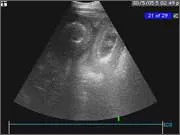

Thoracic and abdominal ultrasonography

This is a key diagnostic technique in the hospital and the technology has advanced to such a degree that we are able to image blood flowing within the heart and collagen fibre misalignment in tendons.